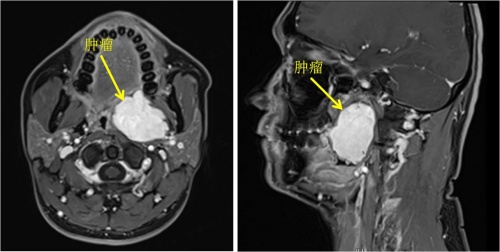

岳阳33岁的李先生最近总感觉咽部不适,而且一张嘴就能看到左侧颈部凸起一个肿块,到医院检查发现咽旁间隙藏着一个46mm×38mm×52mm的肿物。这个潜伏的“炸弹”不仅位置深,还血供丰富,已压迫周围组织,若不及时处理,可能堵塞气道、累及重要神经血管,危及生命。

李先生连忙到湖南省人民医院耳鼻咽喉头颈外科三病区就诊,接诊的周建波主任医师表示,咽旁间隙是上接颅底、下连颈部的“危险三角区”,密布着颈动脉、颈内静脉、迷走神经等关键结构,手术稍有不慎就可能引发大出血、神经麻痹、甚至声嘶、吞咽障碍等,风险极高,而李先生的肿物位置较深,又紧邻重要结构,手术难度超乎常规。传统手术需从颈部开刀,不仅会留下明显疤痕,还可能因视野限制增加神经血管损伤风险。